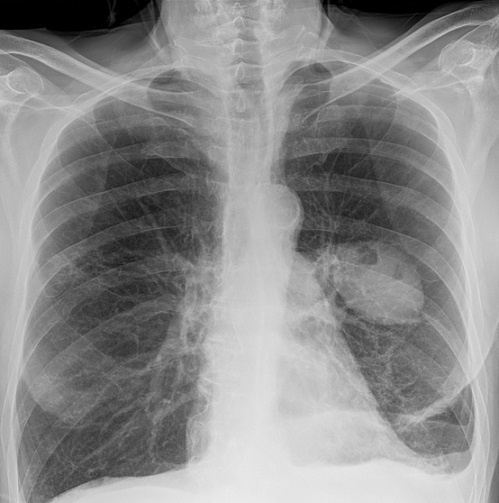

Image radiologique d'une

hydro-pneumothorax gauche avec aspect en niveau

hydro- aerique gauche . Mediastin est devier à droit

et image de elargissement des espace

intercostal gauche . Technique radiologique

standarnisee , cliche PA de face pulmonaire |

Même cas en oblique droit . Image hydro aerique

gauche est tres nette |